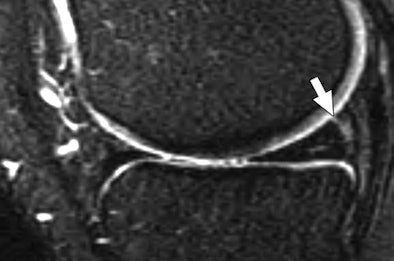

| Thirty-six-year-old man who had injured his knee while squatting down with true-positive MR diagnosis of medial meniscal tear at meniscocapsular junction on MRI 21 days after injury; tear was confirmed at arthroscopy 30 days after injury. Anterior cruciate ligament tear was not identified. Sagittal proton density-weighted (above) and T2-weighted (below) images show linear intermediate-signal-intensity line (arrow in above image) and intermediate- and less-than-fluid-intensity line (arrow in below image) contacting superior surface of meniscus. Fig. 2a, b. De Smet AA, Nathan DH, Graf BK, Haaland BA, Fine JP. Clinical and MRI findings associated with false-positive knee MR diagnoses of medial meniscal tears. AJR. 2008;191(1):93-99. Images courtesy of the American Journal of Roentgenology and the American Roentgen Ray Society. |